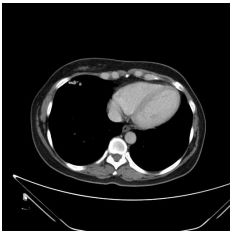

3. This 72-year-old diabetic man was taken to ER for productive cough for 10 days, and rapid progressive dyspnea for 2 days. He also had fever and chill for a week.